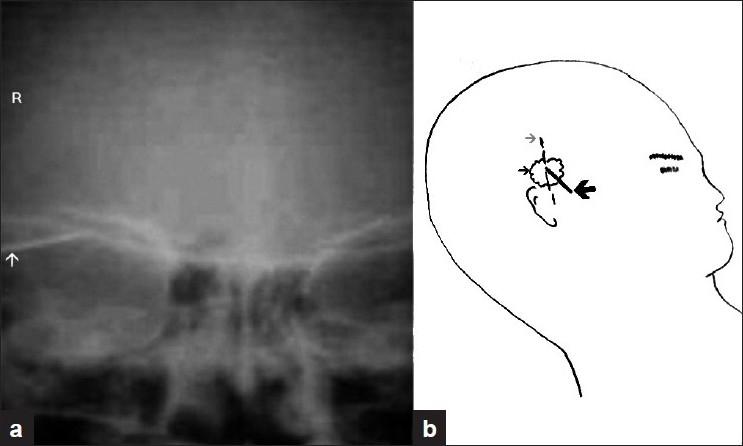

Low velocity penetrating head injury with impacted foreign bodies in situ.

Penetrating head injury is a potentially life-threatening condition. Penetrating head injuries with impacted object (weapon) are rare. The mechanism of low velocity injury is different from high velocity missile injury. Impacted object (weapon) in situ poses some technical difficulties in the investigation and management of the victims, and if the anticipated problems are not managed properly, they may give rise to serious consequences. The management practice of eight patients with impacted object in situ in context of earlier reported similar cases in literature is presented.